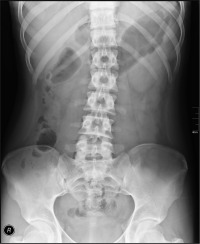

That means we’re not going to do x-rays on every patient, nor are we going to do x-ray examinations on all areas of the spine if we don’t see a reason to do that. During the x-ray examination, we’ll be looking for how your spine is aligned and for anything going on inside of you that would stop us from being able to work on you.

Yes, it’s very likely that we will find “something” on your x-rays when we take them. Since we only take x-rays on those we feel absolutely need them, we are expecting to find something. We don’t usually expect to find pathology like cancer or tumors, but we are looking for biomechanical alignment and potential osteoarthritis or spinal degeneration.

These types of findings will give us a good way of determining how long the patient has had the problem (not necessarily just the symptom) and how long it will take to get them back to as normal as possible.